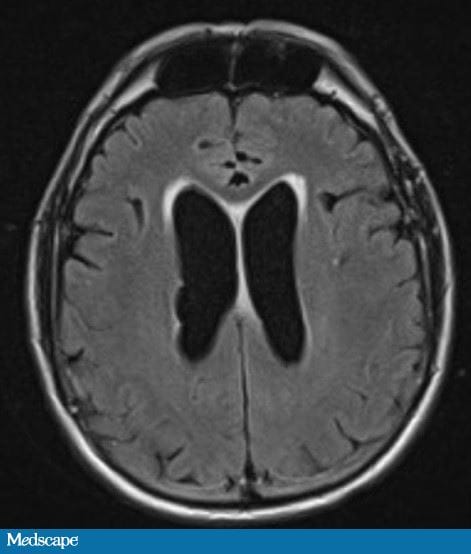

Ressonância magnética (RM) de crânio revela hidrocefalia leve a moderada (Figura 1).